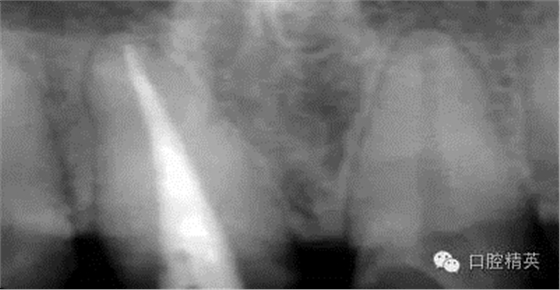

根管治療更是牙體修復(fù)的基礎(chǔ),根據(jù)術(shù)前診斷,對(duì)需要做根管治療的或有必要重新做根管治療的,一定要做到恰充,消除隱患,避免將來(lái)冠修復(fù)好后,出現(xiàn)根尖炎癥的問(wèn)題(見(jiàn)圖3、4、5)。在基礎(chǔ)工作做好后,接下來(lái)開(kāi)始牙體預(yù)備,根據(jù)跟個(gè)人習(xí)慣,選擇合適的車針(圖6、7)。